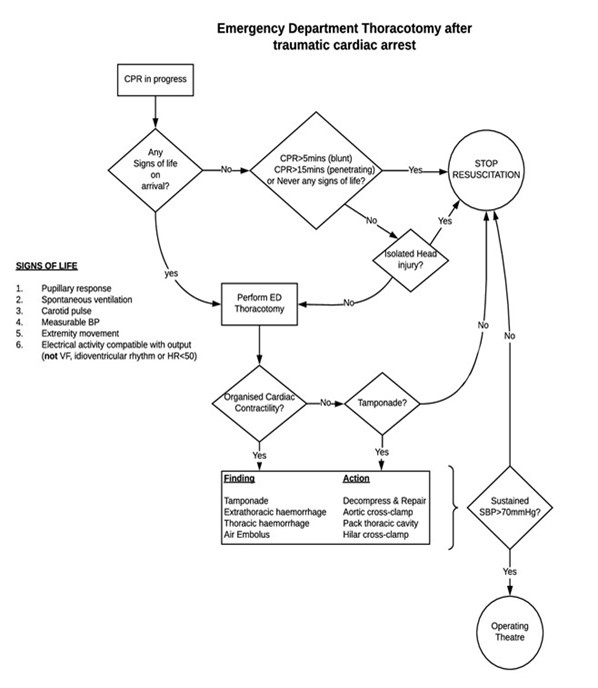

Resuscitative Thoracotomy (RT) is a rarely performed procedure that has an extremely high mortality. The patient’s injuries, however, may be associated with 100% individual mortality if the procedure is not performed. It is a time critical procedure that will likely be performed for the first time in a high-pressure situation. With limited opportunities for training, simplifying both the indications as well as the procedural technicalities is important.

RT is a controversial procedure, and with the evidence base unlikely to ever be the most robust (limited scope for prospective data), the indications are constantly altering especially in blunt trauma. Current evidence indicates the greatest benefit will be for cohorts with short transfer times and cardiac tamponade, which is often diagnosed post thoracotomy. RT is a high-risk procedure, and the risk of transmission of BBVs (Blood Borne Virus) to Health Care Professionals must not be underestimated. While this is a time critical procedure, standard PPE must still be adhered to.